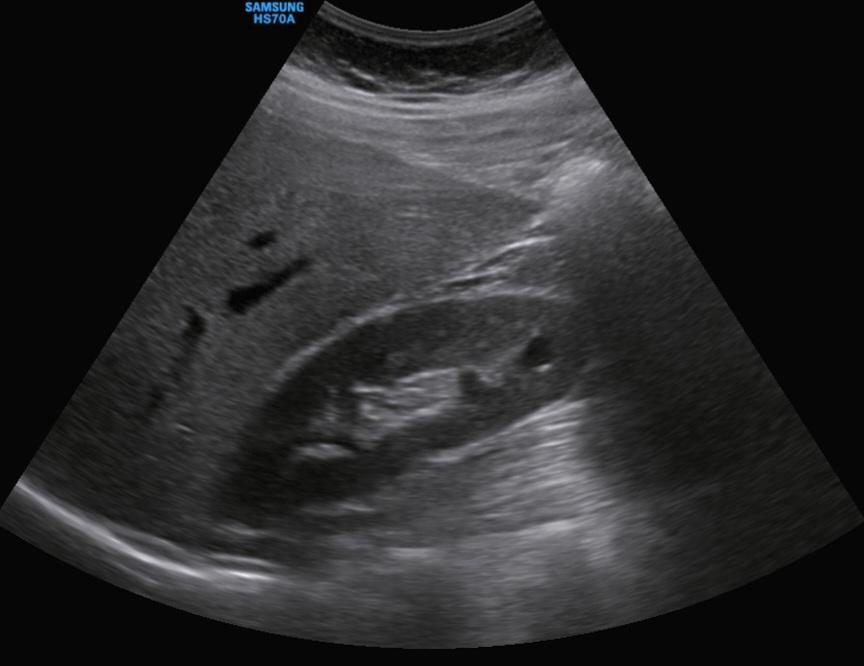

신장 낭종 복부초음파 봐주실분... 안에 하얀선?

복부초음파 사진을 올립니다.

특히 안에 완전 검은색이 아니라 흰색선? 이 있어요..ㅠㅠ여자에요

• 2번 째 사진